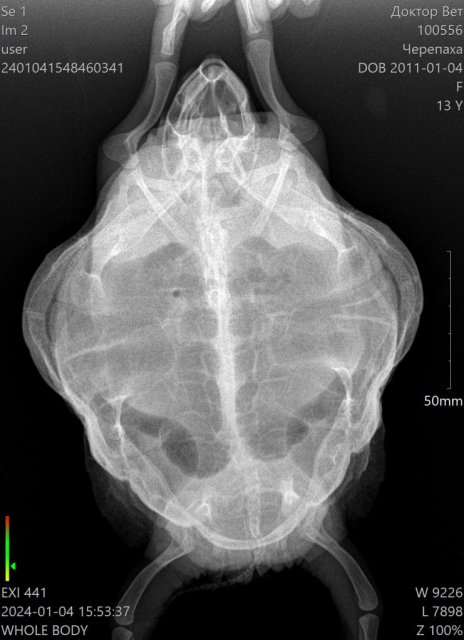

Lara6 Ваше имя: Лариса Локация: Якутск Опубликовано: 4 января 2024 Автор Опубликовано: 4 января 2024 @moth @moth сходили на снимок

Консультанты moth Ваше имя: Мария Локация: Москва Опубликовано: 5 января 2024 Консультанты Опубликовано: 5 января 2024 @Lara6 врачу нашему скинула, но у меня к назначениям вопросы кололи в переднюю лапу? пневмонию поставили по вот этому рентгену что был? если да, то это не герпетолог. По этой проекции лёгкие вообще не видно.